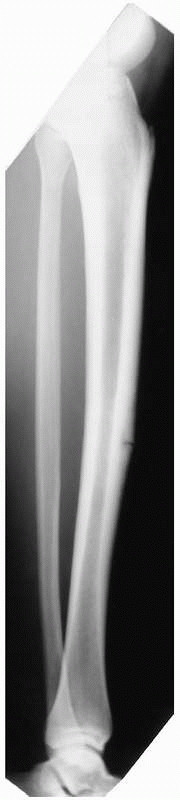

posteromedial compression injuries and occur usually in the proximal or

distal thirds.21,31 When a fracture has developed, a transverse orientation is typical (Fig. 19-2), but longitudinal stress fractures also are reported.102

stress fracture appears in the middle third of the anterior cortex.

nonunion, and complete fractures are also reported.21,84 In chronic cases, a transverse, wedge-shaped defect in the anterior cortex, dubbed the dreaded black line, is often seen in conjunction with cortical hypertrophy150 (Fig. 19-4). Tissue obtained from these sites demonstrates limited healing potential, consistent with a pseudarthrosis.138,154

![]() |

FIGURE 19-4

Lateral radiograph of the left tibia of a collegiate track athlete demonstrates anterior cortical hypertrophy and the dreaded black line of an anterior tension-side stress fracture. |